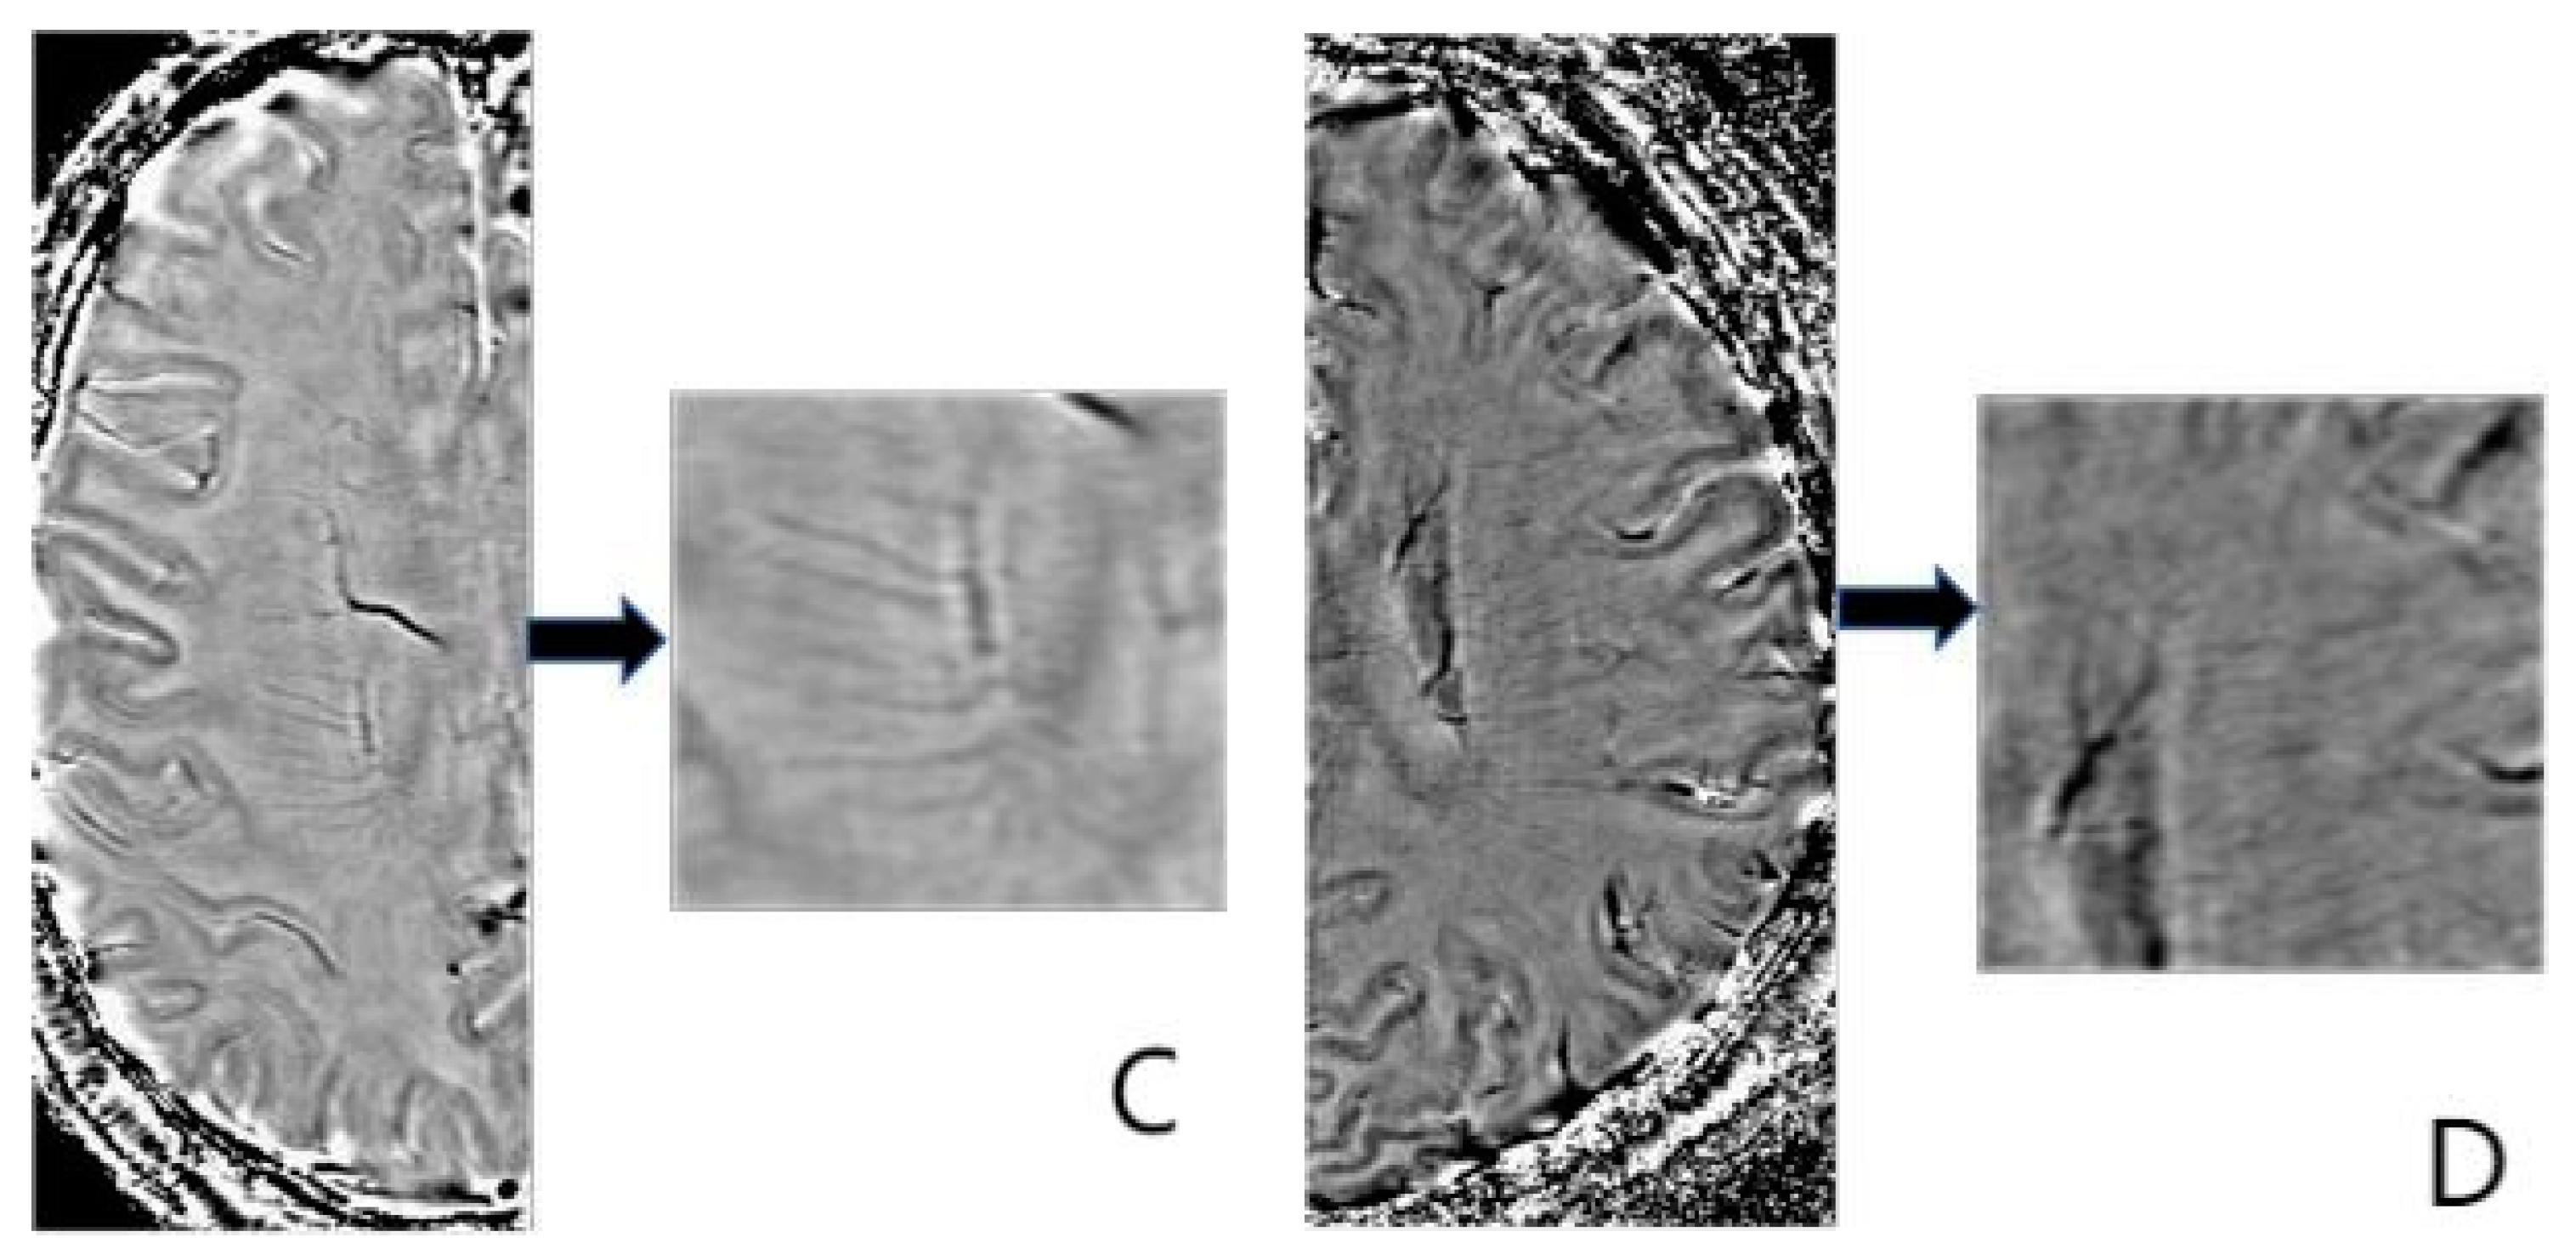

2.5. Deep Medullary Veins Score

- Zhang, R.; Zhou, Y.; Yan, S.; Zhong, G.; Liu, C.; Jiaerken, Y.; Song, R.; Yu, X.; Zhang, M.; Lou, M. A Brain Region-Based Deep Medullary Veins Visual Score on Susceptibility Weighted Imaging. Front. Aging Neurosci. 2017, 9, 269. [Google Scholar] [CrossRef]